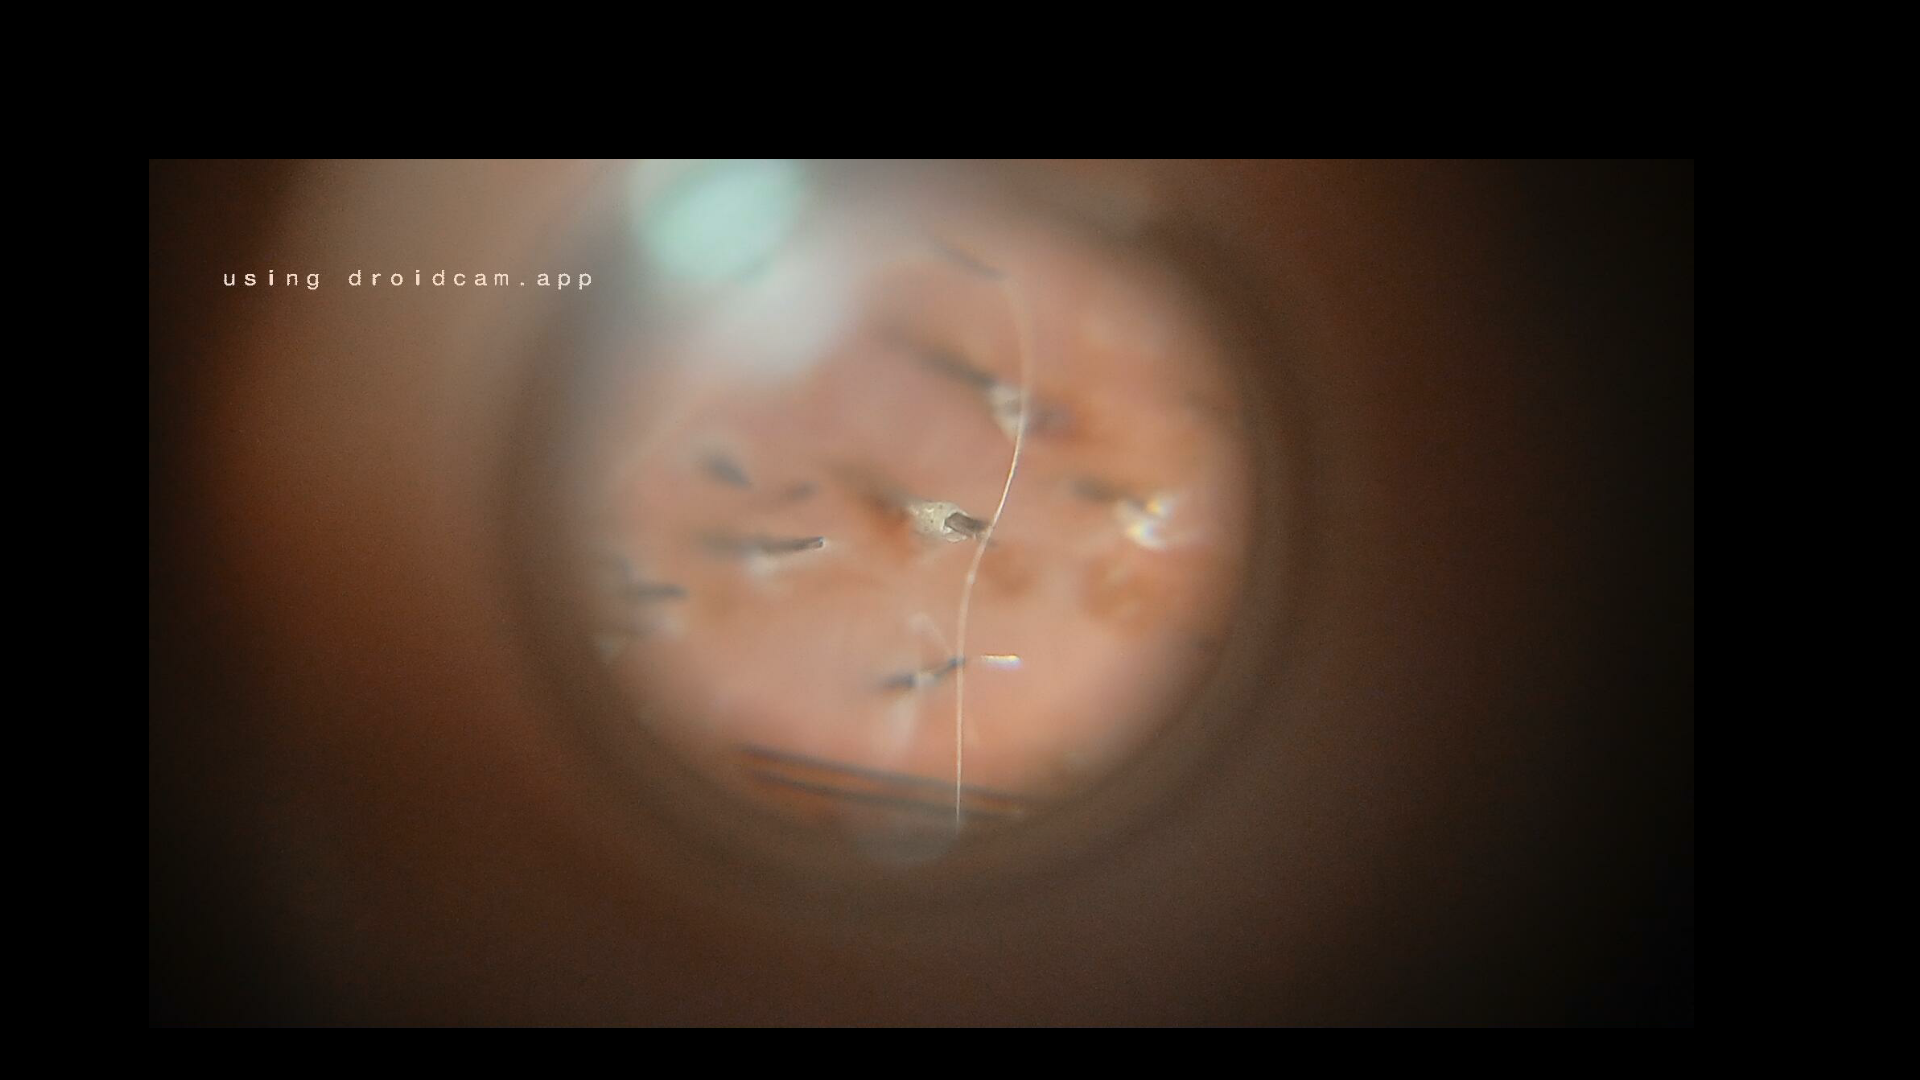

Волос Posted September 7, 2025 Author Report Share Posted September 7, 2025 Ну, и немного фото под микроскопом. Так выглядит донорка через 3 дня после забора графтов. Ранки затянулись. В некоторых местах забора видны темные точки - это так называемые "пустышки", когда доктора промахиваются мимо графта, и высверливают пустой кусок кожи, а графт продолжает расти на прежнем месте. Такое бывает в местах предыдущих заборов графтов, когда кожа, стягиваясь, меняет расположение близлежащих графтов в ней, так же, волосы на теле имеют более изогнутую форму, что мешает докторам их высверливать, и, насколько я знаю, у людей с вьющимися и кудрявыми волосами, и графты имеют более изогнутую форму, что так же усложняет процесс их изъятия. Link to comment Share on other sites More sharing options...

Popular Post Волос Posted September 7, 2025 Author Popular Post Report Share Posted September 7, 2025 Это места посадки новых графтов на 3-й день. Видны "корочки" - куски засохшей на графтах плоти. Полагаю, что такими они становятся уже через несколько часов после пересадки. По крайней мере, сразу в момент посадки, эта плоть на новых графтах, еще разбухшая, и имеет форму шариков, а спустя час, сильно уменьшается в размерах, и визуально не меняется до момента окончательного отхождения. Очень сложно сделать четкие снимки пересаженных графтов, т.к. для этого требуется прижимать микроскоп к коже, что делать очень страшно). 3 Link to comment Share on other sites More sharing options...